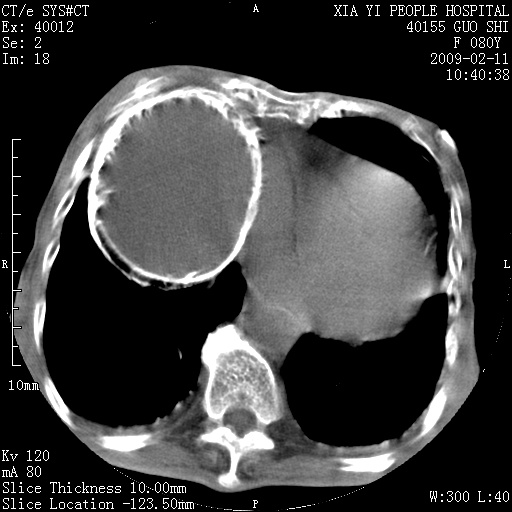

以下是引用随光逐影在2009-2-16 16:34:00的发言:[br]1)考虑右前纵隔皮样囊肿。2)双侧少量胸腔积液。

以下是引用zjzjr在2009-2-16 17:30:00的发言:[br]支持囊性畸胎瘤 双侧少量胸腔积液。